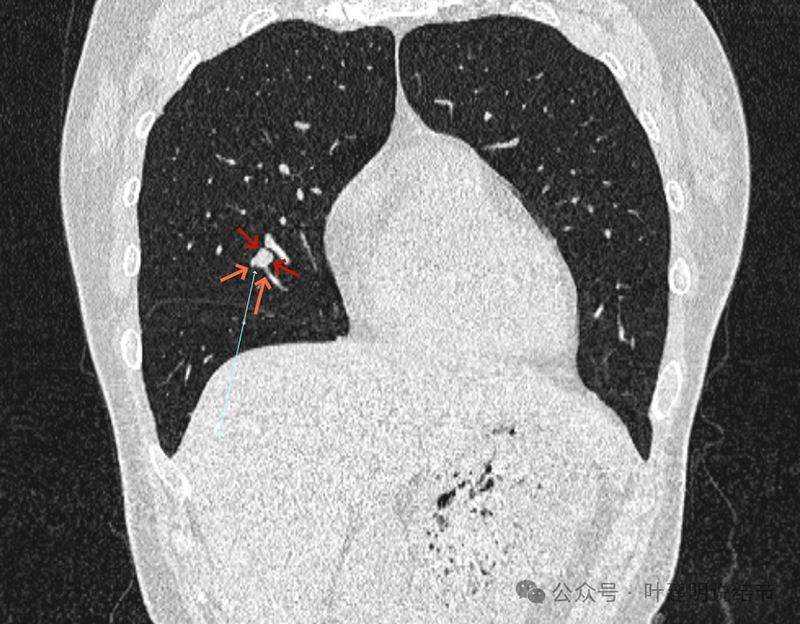

再看冠状位影像:

血管与病灶的关系,两者密度稍不同,天蓝色细箭头所指是分界线。

血管征明显。

血管围着病灶,病灶有膨胀性,表面欠平滑。

不而有膨胀性,血管贴着并被压迫。

边缘欠平滑,邻近血管间隙欠清晰。

血管贴着,结节膨胀。

也示血管与病灶的关系。

结节实性。

纵隔窗这个角度明显见到蓝色箭头所指的血管被病灶侵蚀,而且血管与病灶密度的不同。